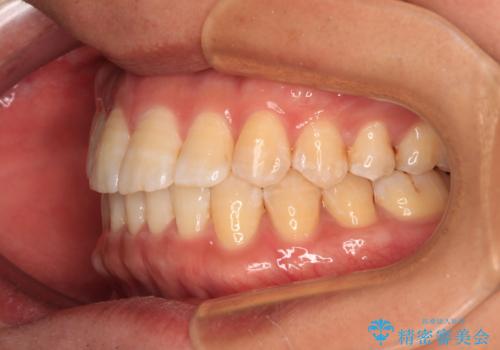

- メタルブラケット

- 1年4ヶ月

- 前歯のデコボコを気にして来院された患者様です。

インビザラインによるマウスピース矯正も適用となる歯列でしたが、できる限り自己管理の煩わしさのない状態で治したいとのことで、ワイヤー装置にて矯正治療を行うこととしました。

予定していた期間より長くかかりましたが、1年強できれいな歯列に仕上がりました。